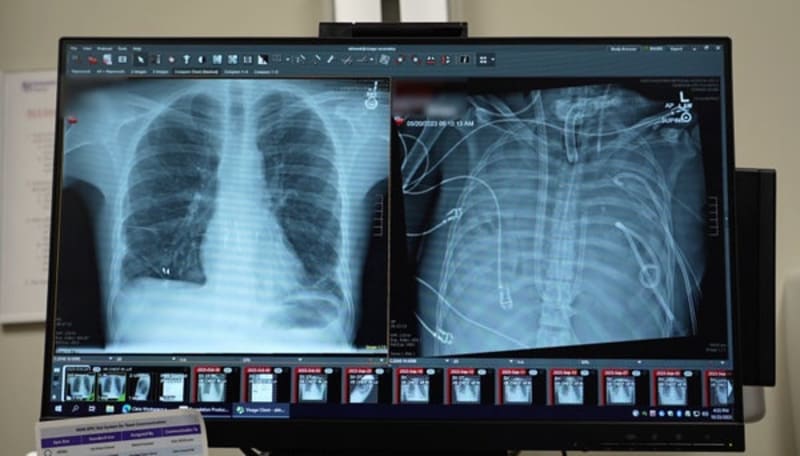

When a 33-year-old man's heart stopped beating at Northwestern Memorial Hospital in 2023, surgeon Ankit Bharat faced an impossible choice. The patient desperately needed new lungs, but he was too sick to survive the transplant surgery itself.

Bharat came up with a radical plan. His team would build artificial lungs that could completely bypass the patient's dying organs. The system would pump blood from the right side of the heart to the left, oxygenate it, and send it throughout the body.

The artificial lungs worked. For two days, they kept the patient alive while his body began healing from the infection. "It was almost like a curse or something that just got lifted," Bharat says. "And suddenly everything started to heal."